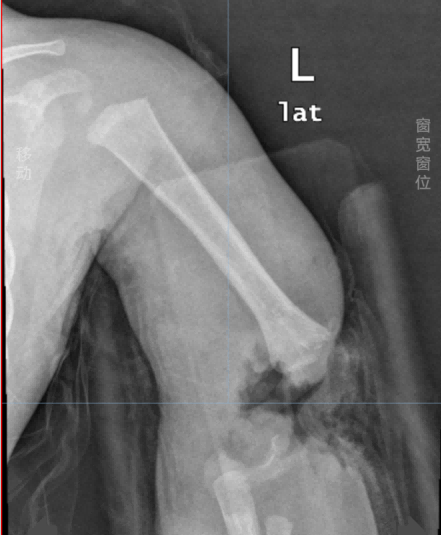

紧急接诊的茂名市人民医院手足显微外科团队迅速为小毅启动绿色通道,影像检查显示,小毅伤情非常危重:左肘部呈现不全离断畸形,仅靠尺侧少量皮肤软组织艰难维系。更令人揪心的是,由于事发后未能第一时间得到有效救治,断肢皮肤已呈苍白状,这是血运缺失、肢体组织濒临坏死的征兆!

▲影像检查结果

“左手臂伤势严重,相当于完全离断,孩子还这么小,必须尽最大努力保住这条手臂!”茂名市人民医院手足显微外科主任关术迅速组织科室医疗骨干团队讨论,最终决定由李日绍、吴辛定两位医生为患儿实施高难度的“左肘部断肢再植术”帮助保肢。